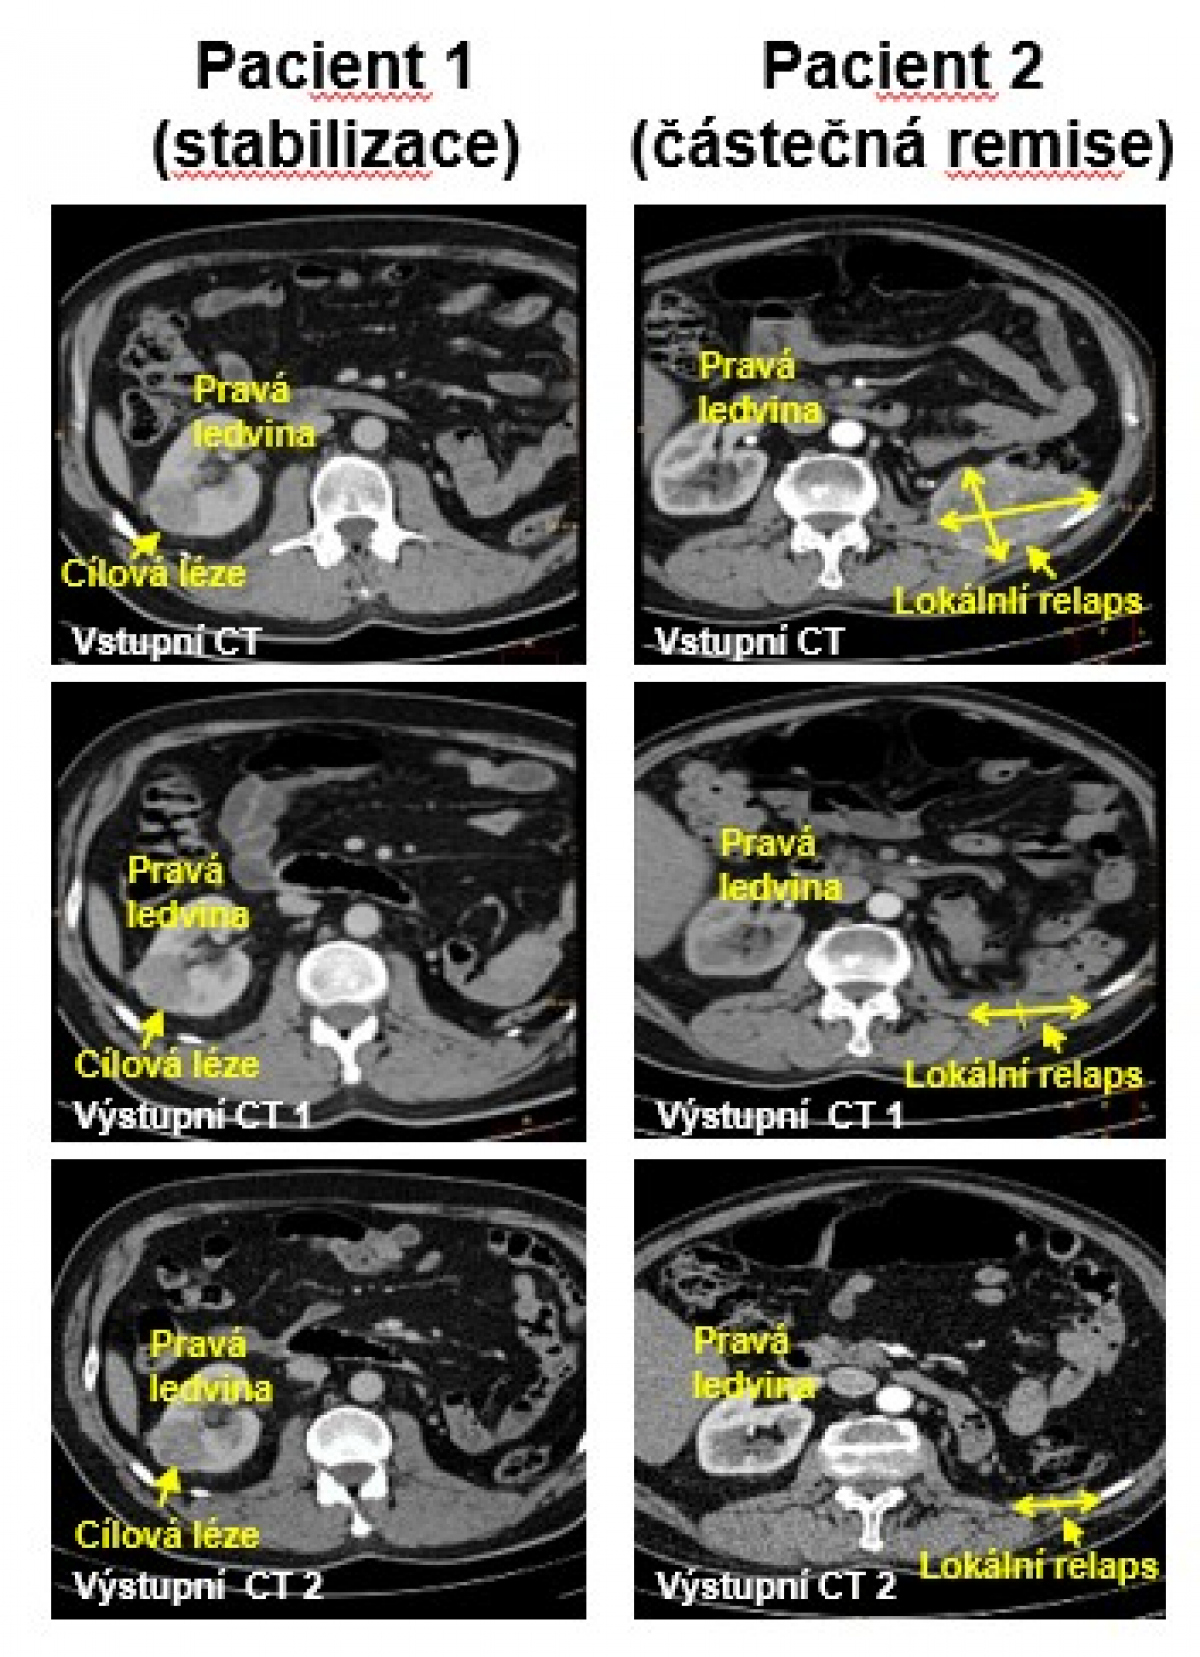

Obrázek: CT skeny nádorů ledvin (metastáz) před léčbou a po léčbě. Pacient 1 – stabilní cílová léze a všechny metastatické nádory. Pacient 2 – lokální relaps v chirurgickém lůžku po odstranění levé ledviny: zmenšení objemu nádoru ze 150 cm3 na 5 cm3, asi 30-tinásobná redukce. Několik metastází je stabilizováno, jedna metastáze v měkké tkáni (poblíž sleziny) není detekovatelná.

První fáze testů MitoTamu trvala dva roky a podílela se na ni Všeobecná fakultní nemocnice v Praze. Do klinického testování byli zařazeni pacienti se solidními a metastatickými nádory. Právě pacienti s metastatickým karcinomem ledvin reagovali na léčbu nejlépe.